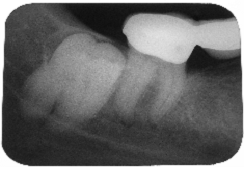

Fig. 12

Aspect radiologic de pe maxilarul superior cu o RPF cu ancorare distala pe un molar.

Observatii

Coroana de invelis metalica este usor supradimensionata;

Jonctiunea intre fata meziala a coroanei si suprafata distala al intermediarilor prezinta o linie de fractura la nivelul angrenarii.

Cauzele posibile

Supraincarcarea biomecanica a intermediarului si o ancorare redusa;

Sudura sau turnatura a cedat sub presiunile masticatorii sau bruxism;

Separarea prea agresiva de catre tehnician, intre coroana si capatul distal al intermediarului.